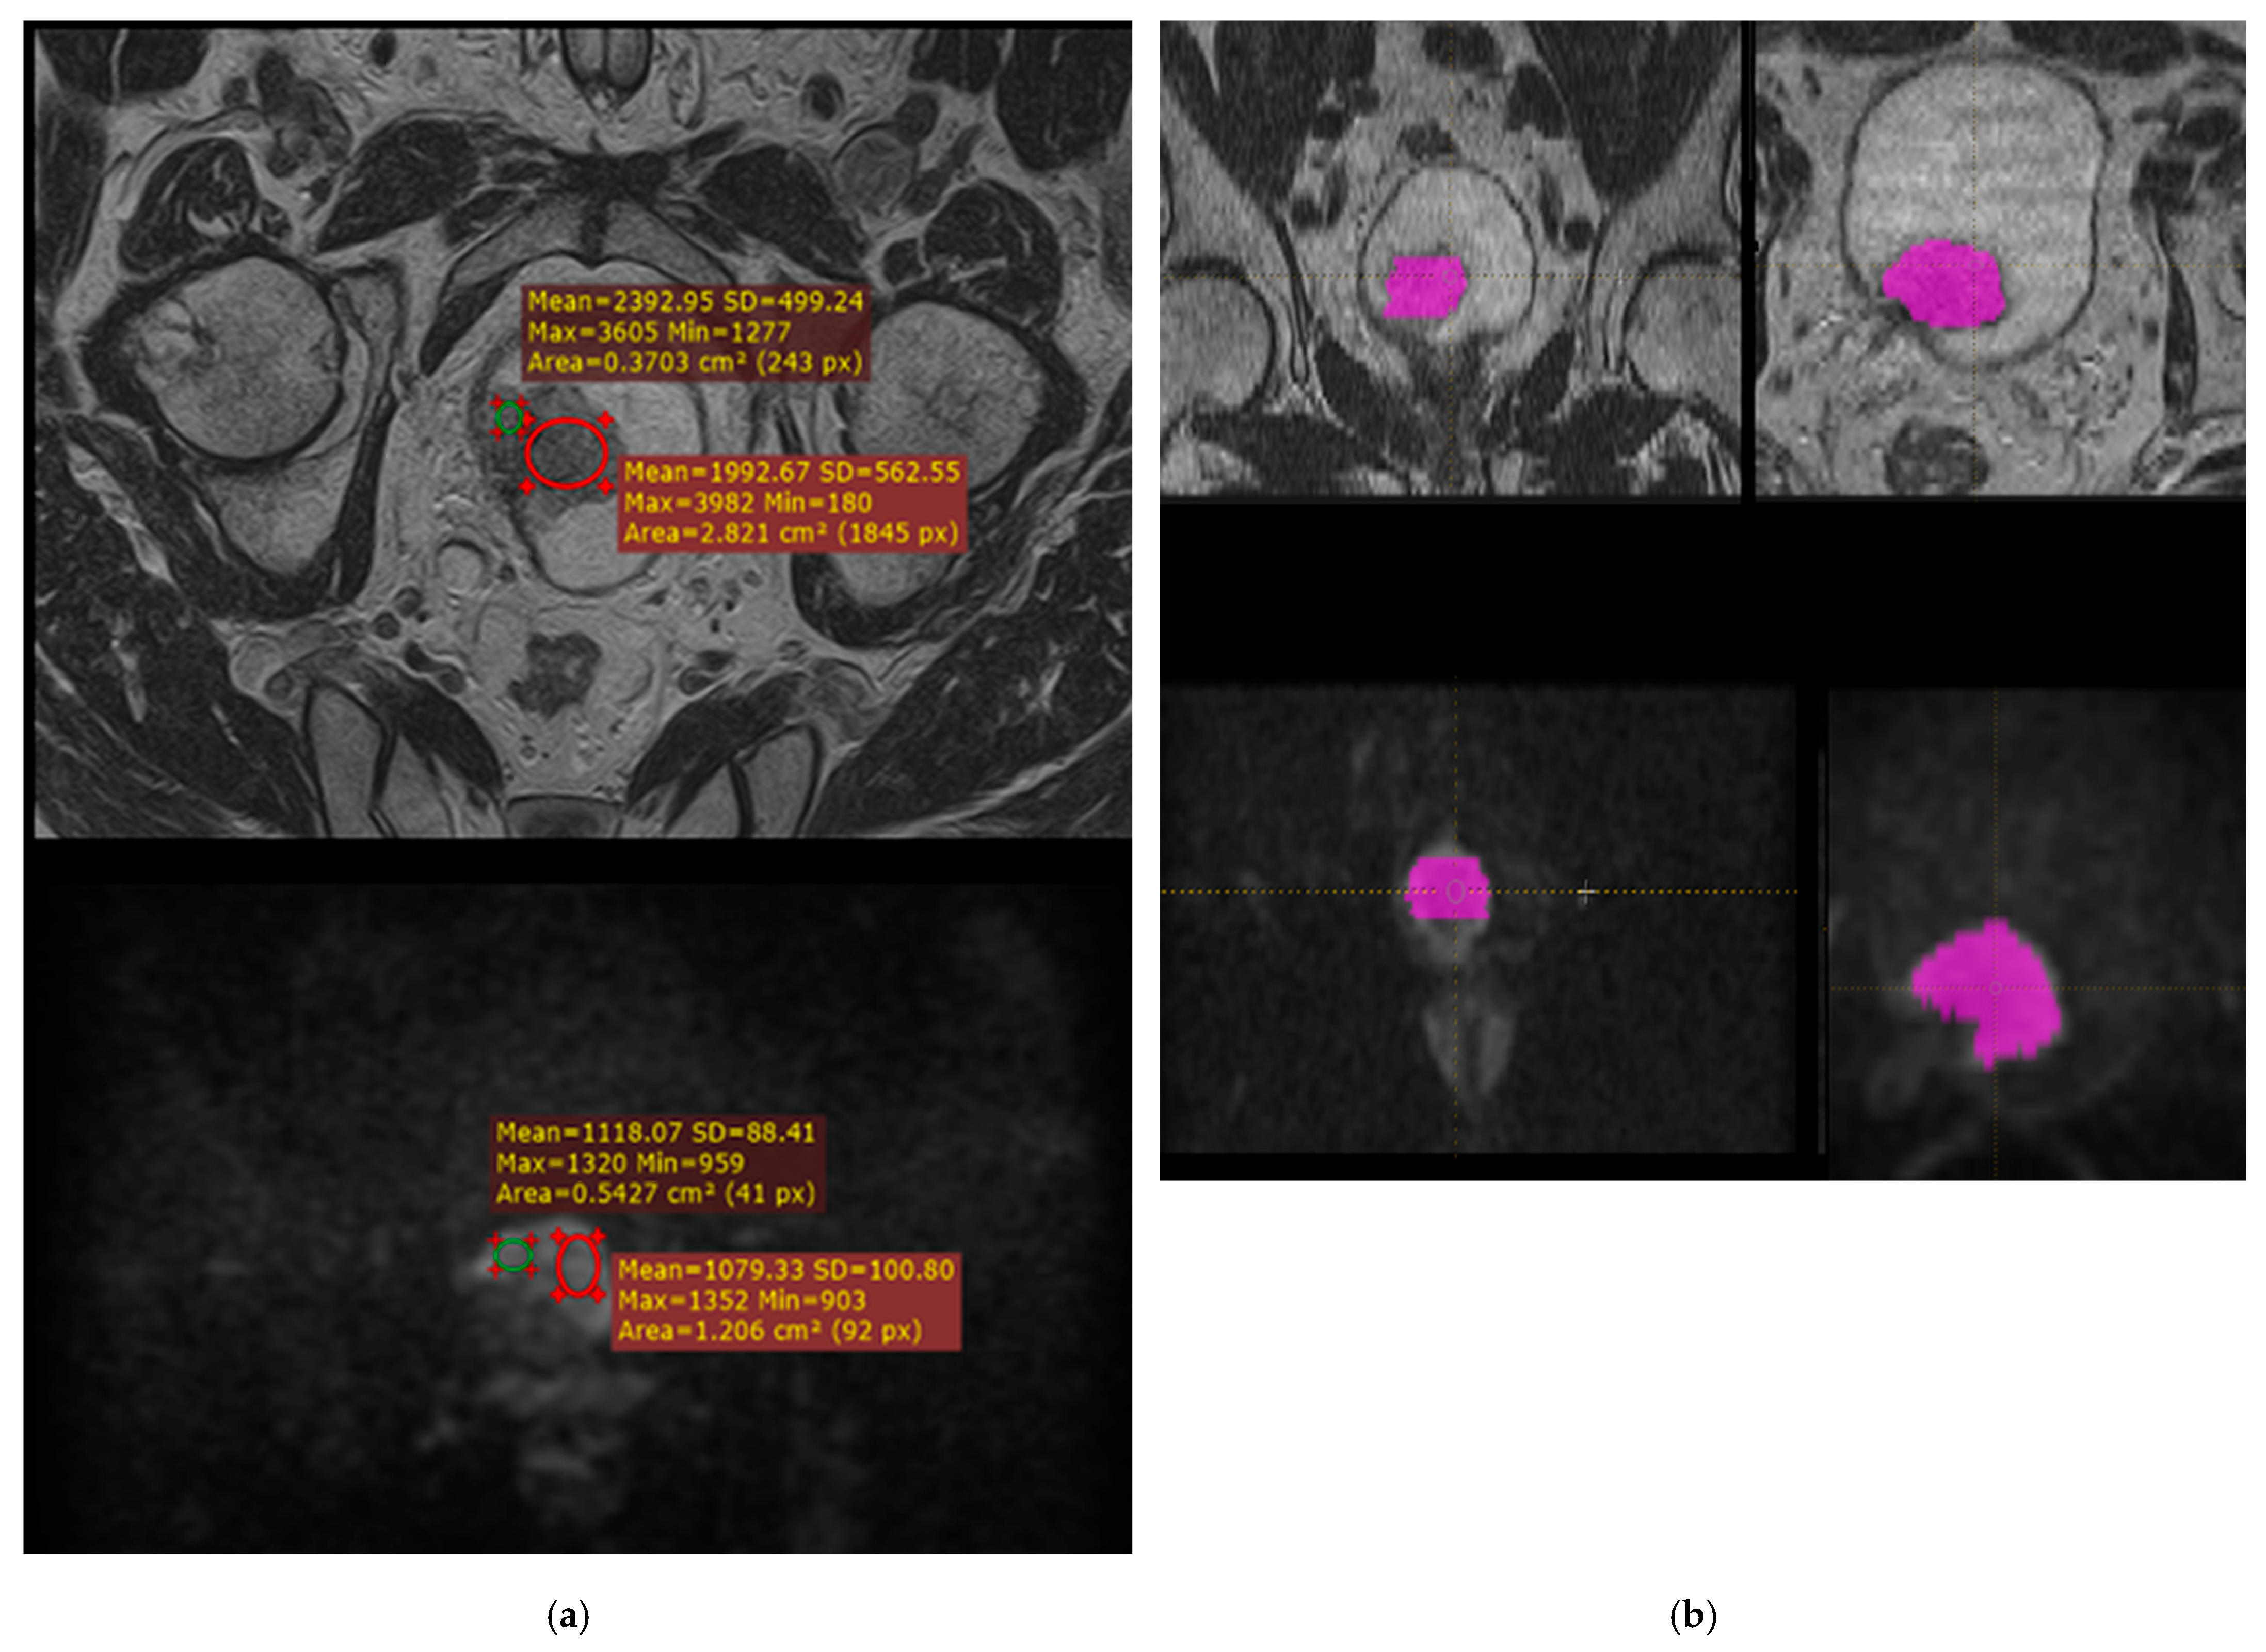

For small tumors, the volume of interest (VOI) was manually delineated on 2–3 slices, and for larger tumors, on up to 5–6 slices. Due to variable slice positioning (caused by bladder filling, motion, or angulation), VOIs were assigned separately for T2-weighted and DWI sequences (Figure 2). Tumor margins were delineated more accurately on T2-weighted images due to the high signal intensity of urine. For ADC maps, the same VOI as for DWI was used.

Figure 2. Radiomics workflow for preoperative MRI assessment of bladder cancer. (a) Example of region of interest (ROI) placement on T2-weighted (top) and diffusion-weighted (bottom) MR images for determination of minimum and maximum signal intensities. These measurements were used to select the bin size for absolute presampling during texture feature extraction. (b) Manual segmentation of the tumor volume of interest (VOI) on T2-weighted (top) and diffusion-weighted (bottom) MRI sequences. The VOI was delineated separately on each sequence by two radiologists for subsequent radiomic texture analysis performed using LifeX 7.1 software.